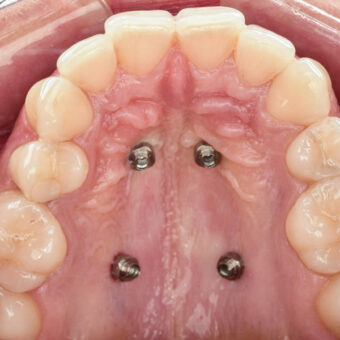

Skuteczna ortodoncja wymaga czasu. Na szczęście dzięki współczesnym, innowacyjnym metodom, które stosujemy w naszej klinice, czas potrzebny do dokonania skutecznej korekty ustawienia zębów można teraz znacznie skrócić. Jednym z takich rozwiązań są miniimplanty ortodontyczne. Te tymczasowe zakotwiczenia mają za zadanie utrzymać jeden lub więcej zębów w ich dotychczasowym położeniu, a równocześnie pomóc w przemieszczeniu innych w zamierzonym kierunku. Do tej pory tego typu procedury były często niemożliwe do przeprowadzenia lub wymagały zabiegów chirurgicznych. Teraz, dzięki miniimplantom, możemy zaprojektować system korekcyjny, który bardzo skutecznie i szybko ustawi zęby w z góry zaplanowanych pozycjach.

Podczas korekcji zgryzu, w szczęce pacjenta montujemy jeden lub więcej miniimplantów. Zabieg jest bardzo precyzyjny, bezbolesny (w miejscowym znieczuleniu komputerowym) i trwa zaledwie kilka chwil. Ze względu na mały rozmiar śruby, pacjenci zazwyczaj nie odczuwają żadnych dolegliwości czy dyskomfortu. Specjalna struktura miniimplantu zapobiega jego integracji z kością, dlatego – kiedy urządzenie spełni swoje zadanie – można je łatwo usunąć.

Miniimplanty pozwalają znacznie skrócić proces leczenia ortodontycznego. Dają też możliwość dokonywania drobnych korekt w pozycji niektórych zębów bez konieczności zakładania aparatu stałego na cały łuk zębowy.